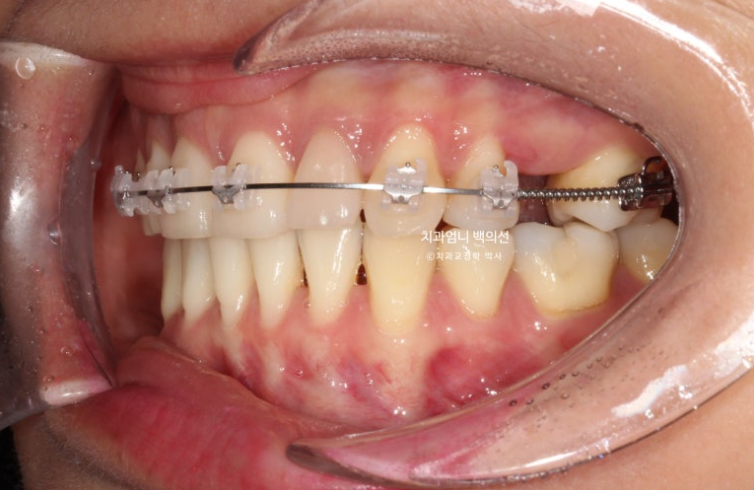

24.04

치료시작 6개월차 모습입니다.

위에만 장치를 붙여서 치료를 진행합니다.

큰어금니 공간을 회복하면서 말이죠.